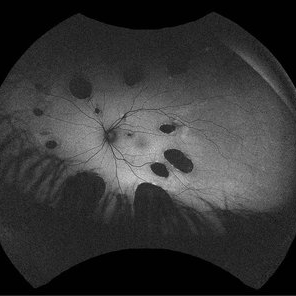

Idiopathic multifocal choroiditis (IMFC)

23 -year- old man with gradually decreased vision specially in right eye, multiple lesions are in the retinal and choroidal tissue. IMCP causes episodes of inflammation that can occur bilaterally, simultaneously or separately

Photographer: Mohammadkarim Johari, Shiraz university of medical science

Condition/keywords: inflammatory choroidopathy, multifocal chorioretinitis (MCP), multifocal choroiditis